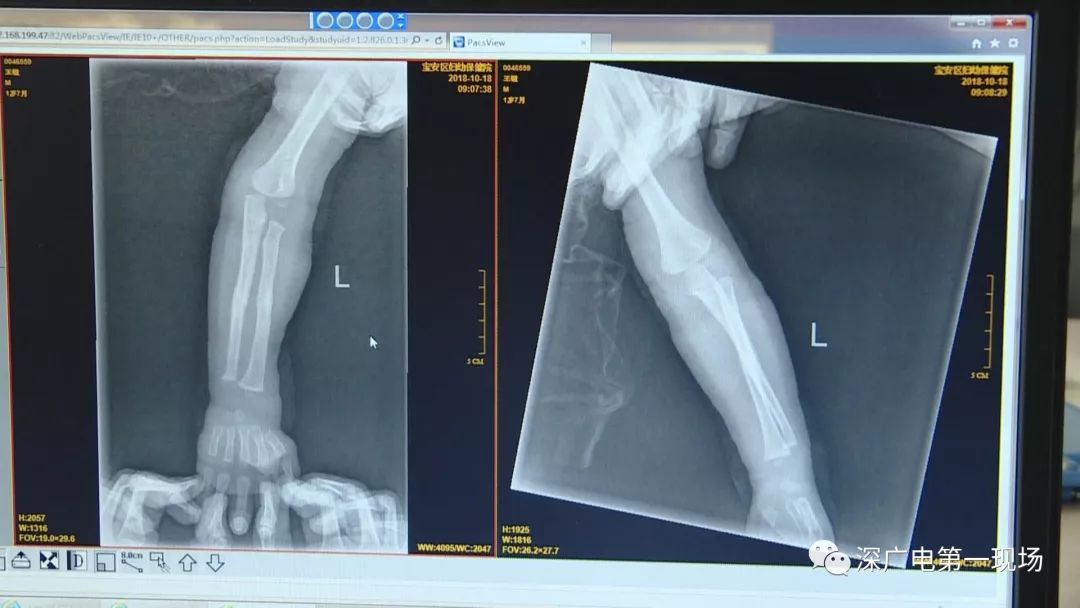

9月4號(hào),一名1歲零5個(gè)月的男嬰因在家中摔傷,被父母送到了寶安區(qū)婦幼保健院,醫(yī)生診斷為左側(cè)尺橈骨骨折。在進(jìn)行全麻手術(shù)之前,院方例行對(duì)嬰兒進(jìn)行了周身檢查。手術(shù)前,兒外科醫(yī)生趙冠聰在查看患者的胸片時(shí),發(fā)現(xiàn)這名嬰兒的胃部有一枚硬幣大小的暗影。